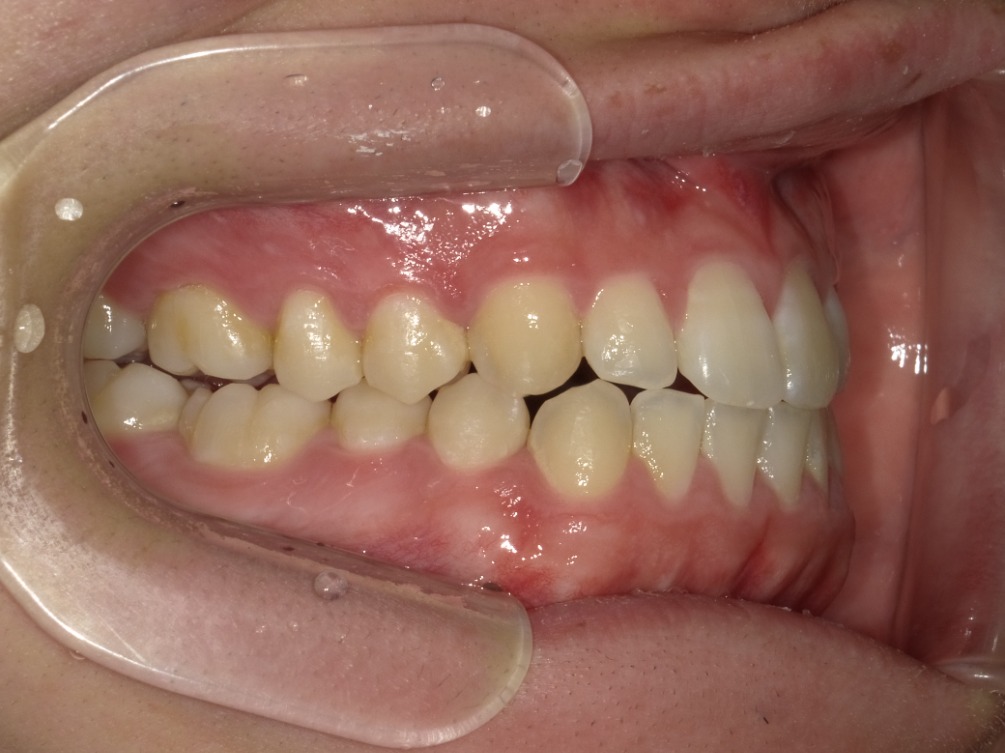

右横

| 治療内容 | インビザライン 全顎 |

| 治療詳細 | 反対咬合や叢生を整えるために、歯の表面にアタッチメント(白い突起)をつけ、IPR(歯と歯の間を削る)を行いました。 また、顎間ゴムと呼ばれる上顎と下顎に渡って引っ掛けるゴムの補助装置も用いて治療を行いました。 |

| 患者情報 | 10代 男性 デンタルモニタリング使用 |

| 主訴 | 下顎が前に出ている(受け口) 歯のがたつき |